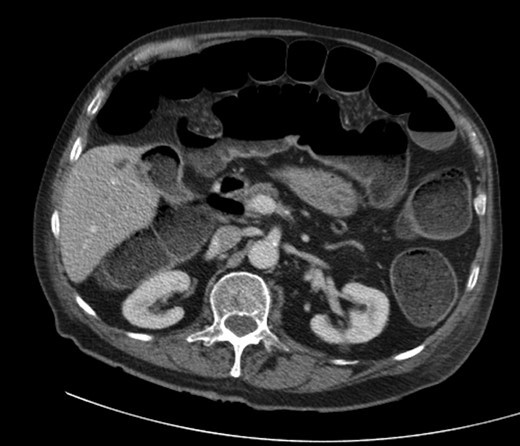

A 92-year male, with no significant co-morbidities apart from peptic ulcers, was admitted with 6 days of obstination. On examination he was dehydrated, with a hugely distended abdomen but no signs of peritonitis. Blood showed features of dehydration and plain abdominal X-ray demonstrated both small and large bowel dilatation, but no obvious causal pathology. A contrast-enhanced computed tomography scan revealed a 2.5-cm partially calcified gallstone impacted at the descending colon-sigmoid junction (Fig. 1). There was no stricture or diverticular disease distal to the stone. A cholecysto-colic fistula could be seen (Fig. 2), with a further smaller gallstone in the caecum (Fig. 3). The offending gallstone could be seen incidentally in the gallbladder on imaging 3 years previously (Fig. 4).

Large gallstone impacted in the descending colon-sigmoid junction, causing large bowel obstruction proximally.